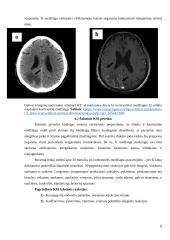

Kompiuterinė tomografija - tai toks diagnostinis vaizdinimo metodas, kai tiriamasis objektas yra daug kartų nuskenuojamas skirtingais kampais siauru rentgeno spindulių pluoštu ir pagal gautus duomenis kompiuteris rekonstruoja pjūvio vaizdą (K. Skauminas, D. Kaškelytė, E. Keleras ir kt., 2008). KT taikoma ligų diagnostikai, įvairių audinių diferenciacijai, intervencinėje radiologijoje, neurologijoje, ortopedijoje, chirurgijoje, onkologijoje prieš radioterapijos naudojimą. Kompiuterinės tomografijos metu galima atlikti biopsiją 1 iš tiksliai...